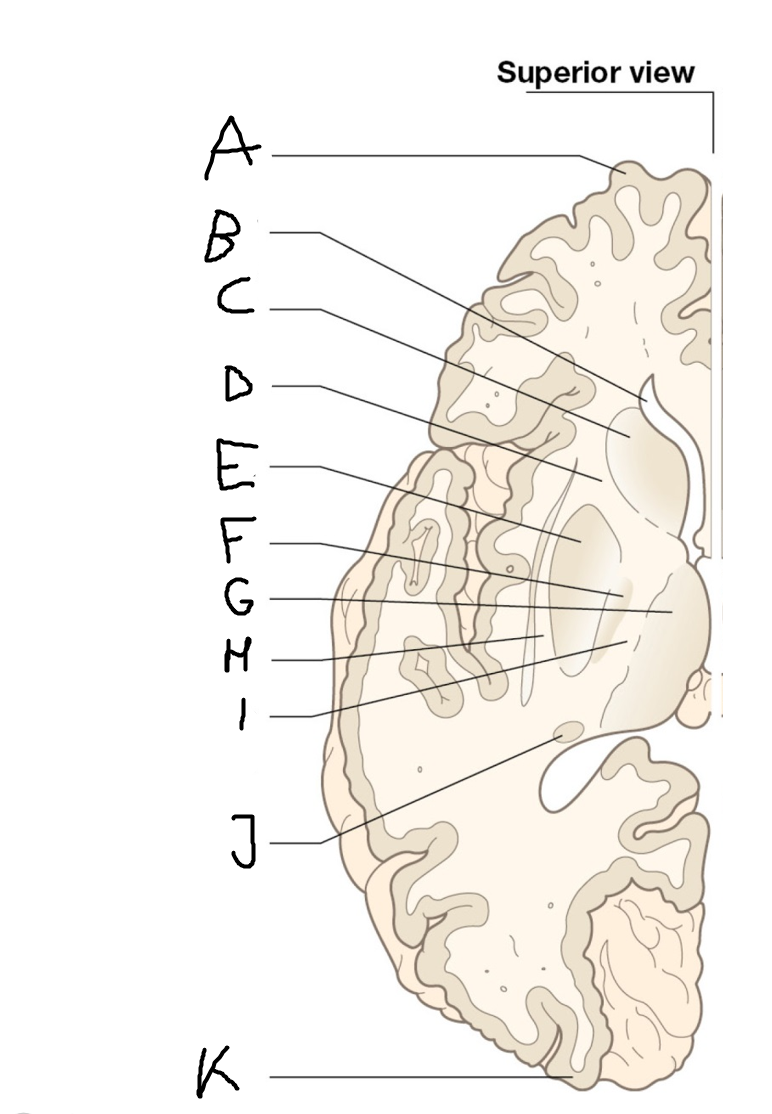

internal capsule (posterior limb)

B

anterior horn of lateral ventricle

C

head of caudate nucleus

D

internal capsule (anterior limb)

E

putamen

F

globus pallidus

G

Thalamus

H

External capsule

I

internal capsule (posterior limb)

J

tail of caudate nucleus